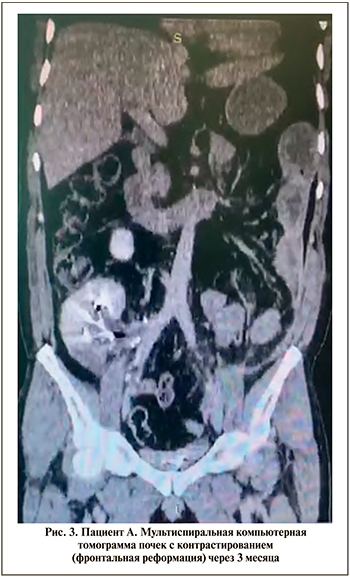

Дальнейший послеоперационный период протекал без осложнений, больные выписывались на 14–16-е сутки после операции в удовлетворительном состоянии. Через месяц больным выполнена цистоскопия, стент удален из реплантированного мочеточника. Результаты контрольных МСКТ почек с контрастированием: реплантированная почка функционировала адекватно (рис. 3).